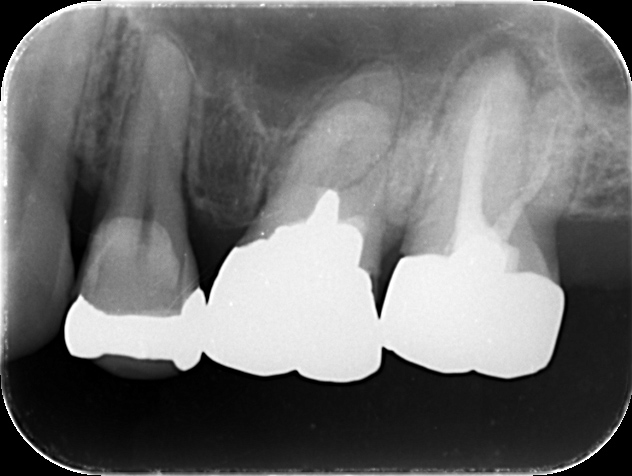

下の写真の歯の中にある黒い筋が「根管」です。

根管の形状は患者さんごとに異なり、非常に複雑です。さらに、狭い部分は直径1mmもありません。狭くて複雑な根管から、神経組織を取り除く治療がいかに難しいか、おわかりいただけると思います。

下の写真は、マイクロスコープで見た根管の様子です。いかに治療の精度が高まるか、一目瞭然だと思います。